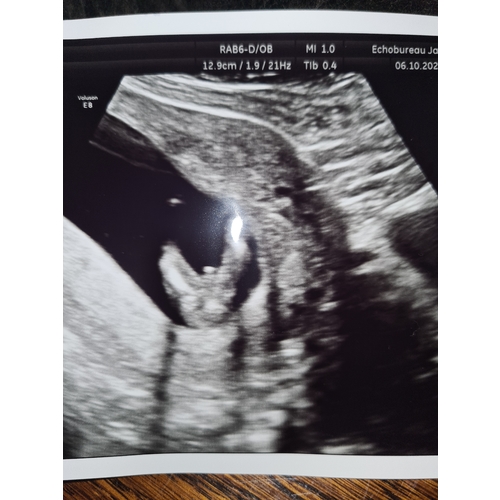

Dit was de 12 weken echo. 🤣ik was ook overtuigd van een jongetje.. het maakt me verder niet zoveel uit, ben al lang blij dat hij/zij in orde lijkt. En die taart lijkt me best lekker 😂😂bedankt voor je felicitatie! 🥰

Bij mij ging ze ook meteen voor het zij aanzicht. De echoscopiste zei meteen dan kan ik het het beste meteen zien. Is een meisje. Mijnes is wel gedaan vandaag op 16+2 Dus is zeker geen nub meer. Ze zei dat dat witte staafje een schaambeen/bot is en dat bij jongetjes daarboven heel duidelijk een piemeltje met balletjes had gezeten. Daarna nog wat shots van onder gezien en ook daar was echt 0,0 te zien aan een uitsteeksel 🤣 maar zij pakte dus ook niet een pottyshot om het te zien...

Dat ding wat erboven zweeft is trouwens een gebogen beentje🤣